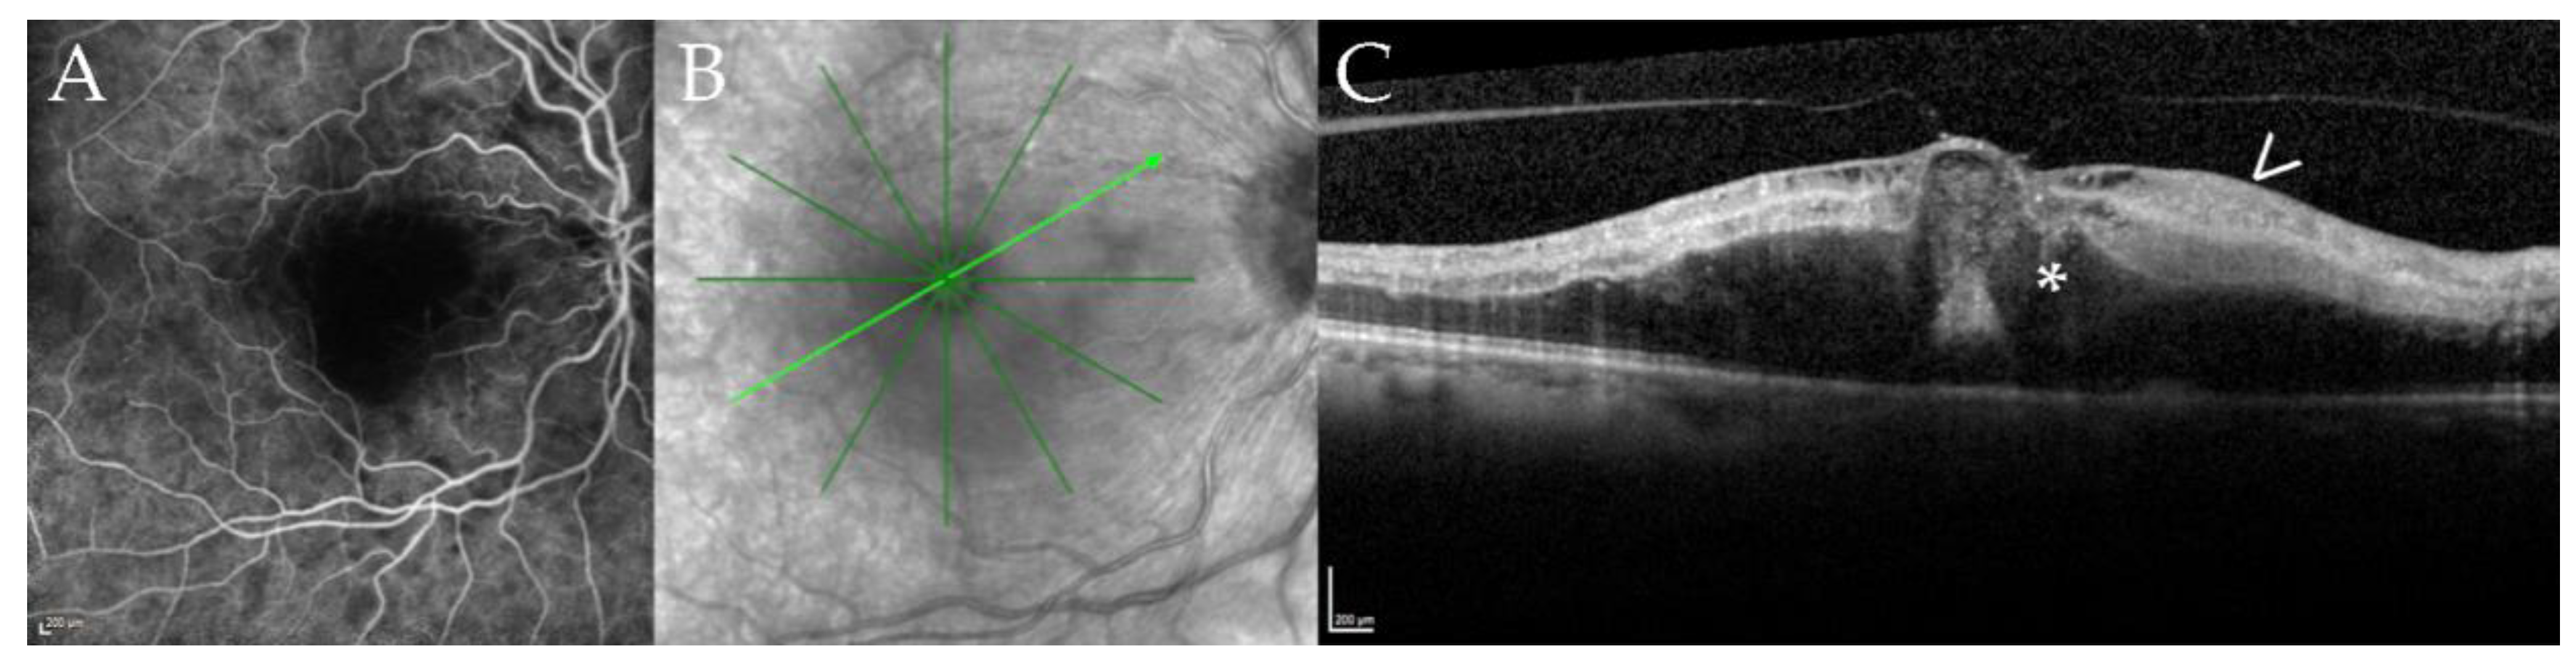

During follow-up, two patients developed a neovascularization (NV) (case 3, left eye retinal NV after 86 months (Figure 2); case 4, type 2 macular NV right eye after 36 months, (Figure 3)) [12].

Figure 3. Macular neovascularization associated with choroidal granuloma. Optical coherence tomography angiography (OCTA, panel (A)) of a 53-year-old male patient (case 4) at 36 months of follow-up demonstrating a macular neovascular vessels Type 1 in the en face OCTA scan of the outer retina choriocapillaris slab (red rectangle). Note the branching of many small capillaries and the presence of peripheral arcades in the higher magnification of the neovascular membrane. The corresponding B-scan with superimposed flow information (panel (B1,B2)) demonstrates subretinal fluid (B1) and subretinal hyperreflective material (*, (B2)) overlying a large choroidal granuloma. Note the subretinal hyperreflective material (*, (B2)) and the associated subretinal fluid (+, (B1)) leading to decreased vision. Multiple hyperfluorescent lesions at the posterior pole and middle periphery are visible in fluoresceine angiography (FA, panel (C)). Note the leakage of the lesion at the posterior pole related to the active neovascularization (arrow). Indocyanine green angiography (ICGA, panel (D)) shows disseminated hypofluorescent choroidal lesions including the large granuloma associated with the CNV; the lesions are more numerous compared to FA.

One patient presented himself with a cilioretinal vessel occlusion at the 18 months follow-up (case 12, right eye, at 18 months follow-up (Figure 4)).

Figure 4. Cilioretinal vessel occlusion in a 67-year-old patient with disseminated Mycobacterium chimaera infection. Fluoresceine angiography (FA, panel (A)), near infrared imaging (NIR, panel (B)), optical coherence tomography B-scan (OCT, panel (C)) of case 12 at 18 months of follow-up. Panel (A) shows a filling defect of the cilioretinal vessel in the early frames of the FA; the inferotemporal and superotemporal arteries are already filled. Panel (B) shows the NIR image with the location of the B-scan (light green arrow) shown in panel (C). Note the defocusing of the macular region. The corresponding B-scan (Panel (C)) demonstrates hyperreflectivity of the inner retinal layers (arrow) and macular edema (asterisk) secondary due to ischemia after cilioretinal vessel occlusion.